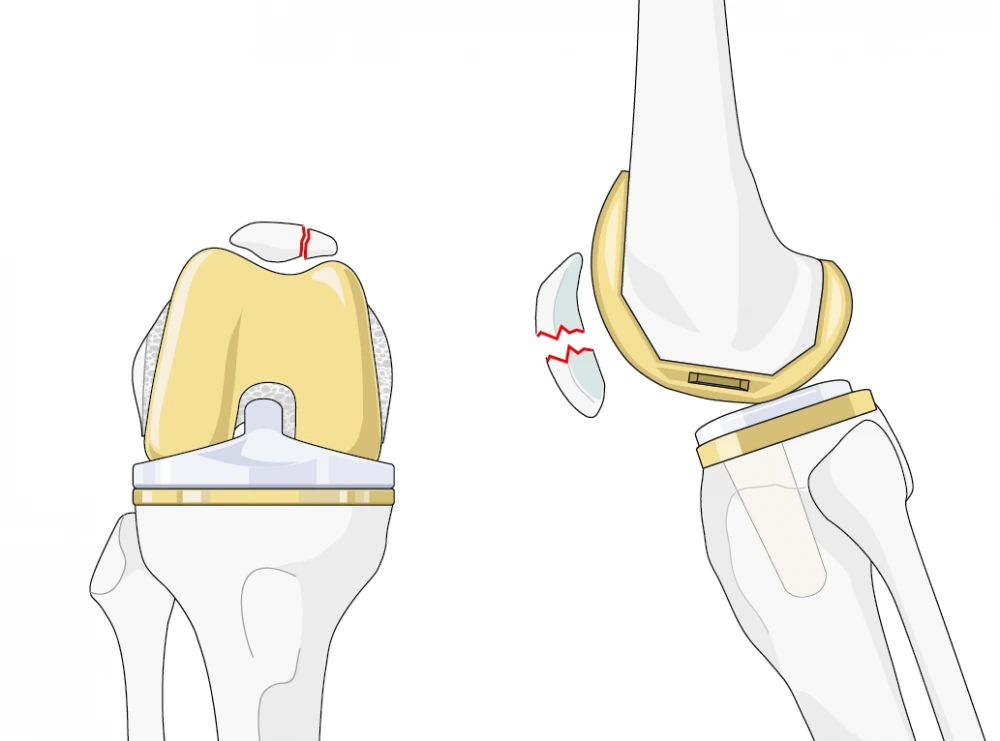

Patellar resurfacing involves replacing the damaged or arthritic surface of the patella (kneecap) with a prosthetic component made of high-quality materials such as polyethylene or metal. The goal is to restore smooth movement and alignment of the patella with the femur, reducing pain and improving overall knee function. It is commonly performed during total knee replacement (TKR) or partial knee replacement surgeries when the patella is found to be worn or damaged.